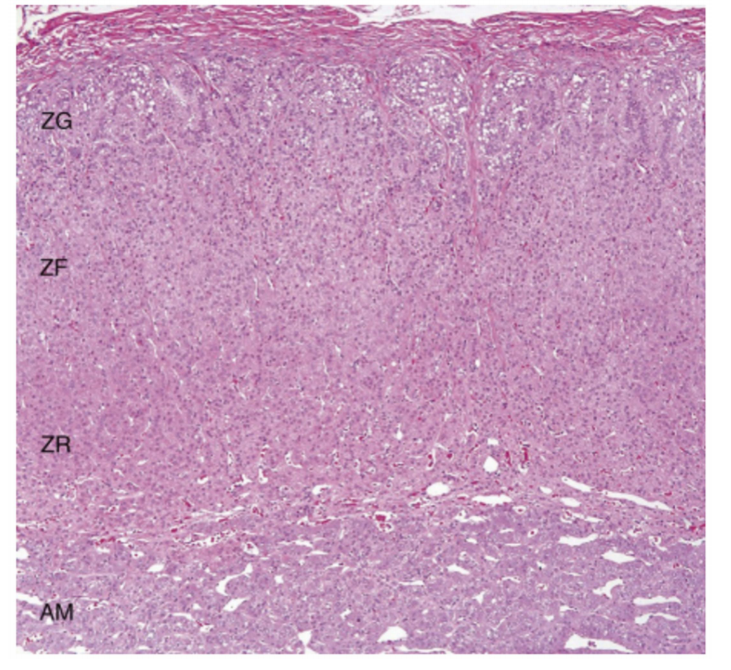

肾上腺负责产生和分泌一些激素。肾上腺由分泌儿茶酚胺的肾上腺髓质和分泌糖皮质激素、盐皮质激素和性激素的肾上腺皮质组成。